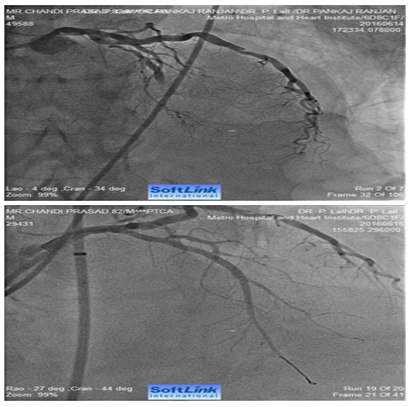

Figure 4 Caudally angulated RAO view of an 80 years old male showing extensive calcification involving distal LMCA extending into ostial LAD and ostial and proximal LCX (bifurcation lesion). The right panel shows fully opened-up LMCA, LAD and LCX after RA with a 1.25 mm burr and deployment of two drug eluting stents (one from LMCA to LAD and second one in proximal LCX (covering its ostium).